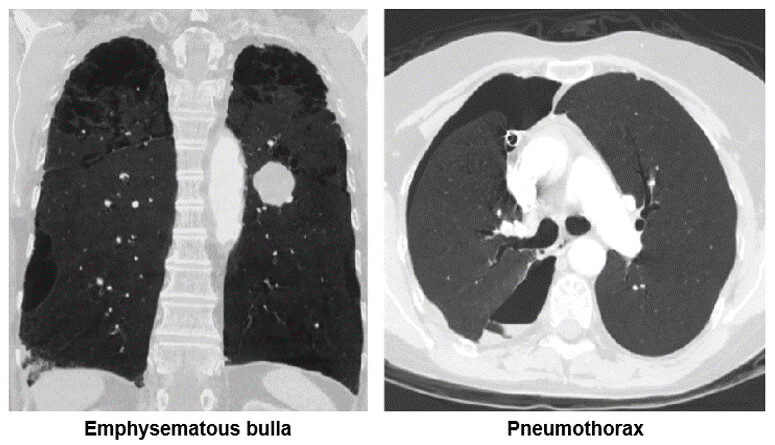

Chest

Both of these images show how the minimum intensity projection technique is used for the diagnosis of emphysema. Notice the bullae in the image on the left and the pneumothorax in the left lung on the image on the right.